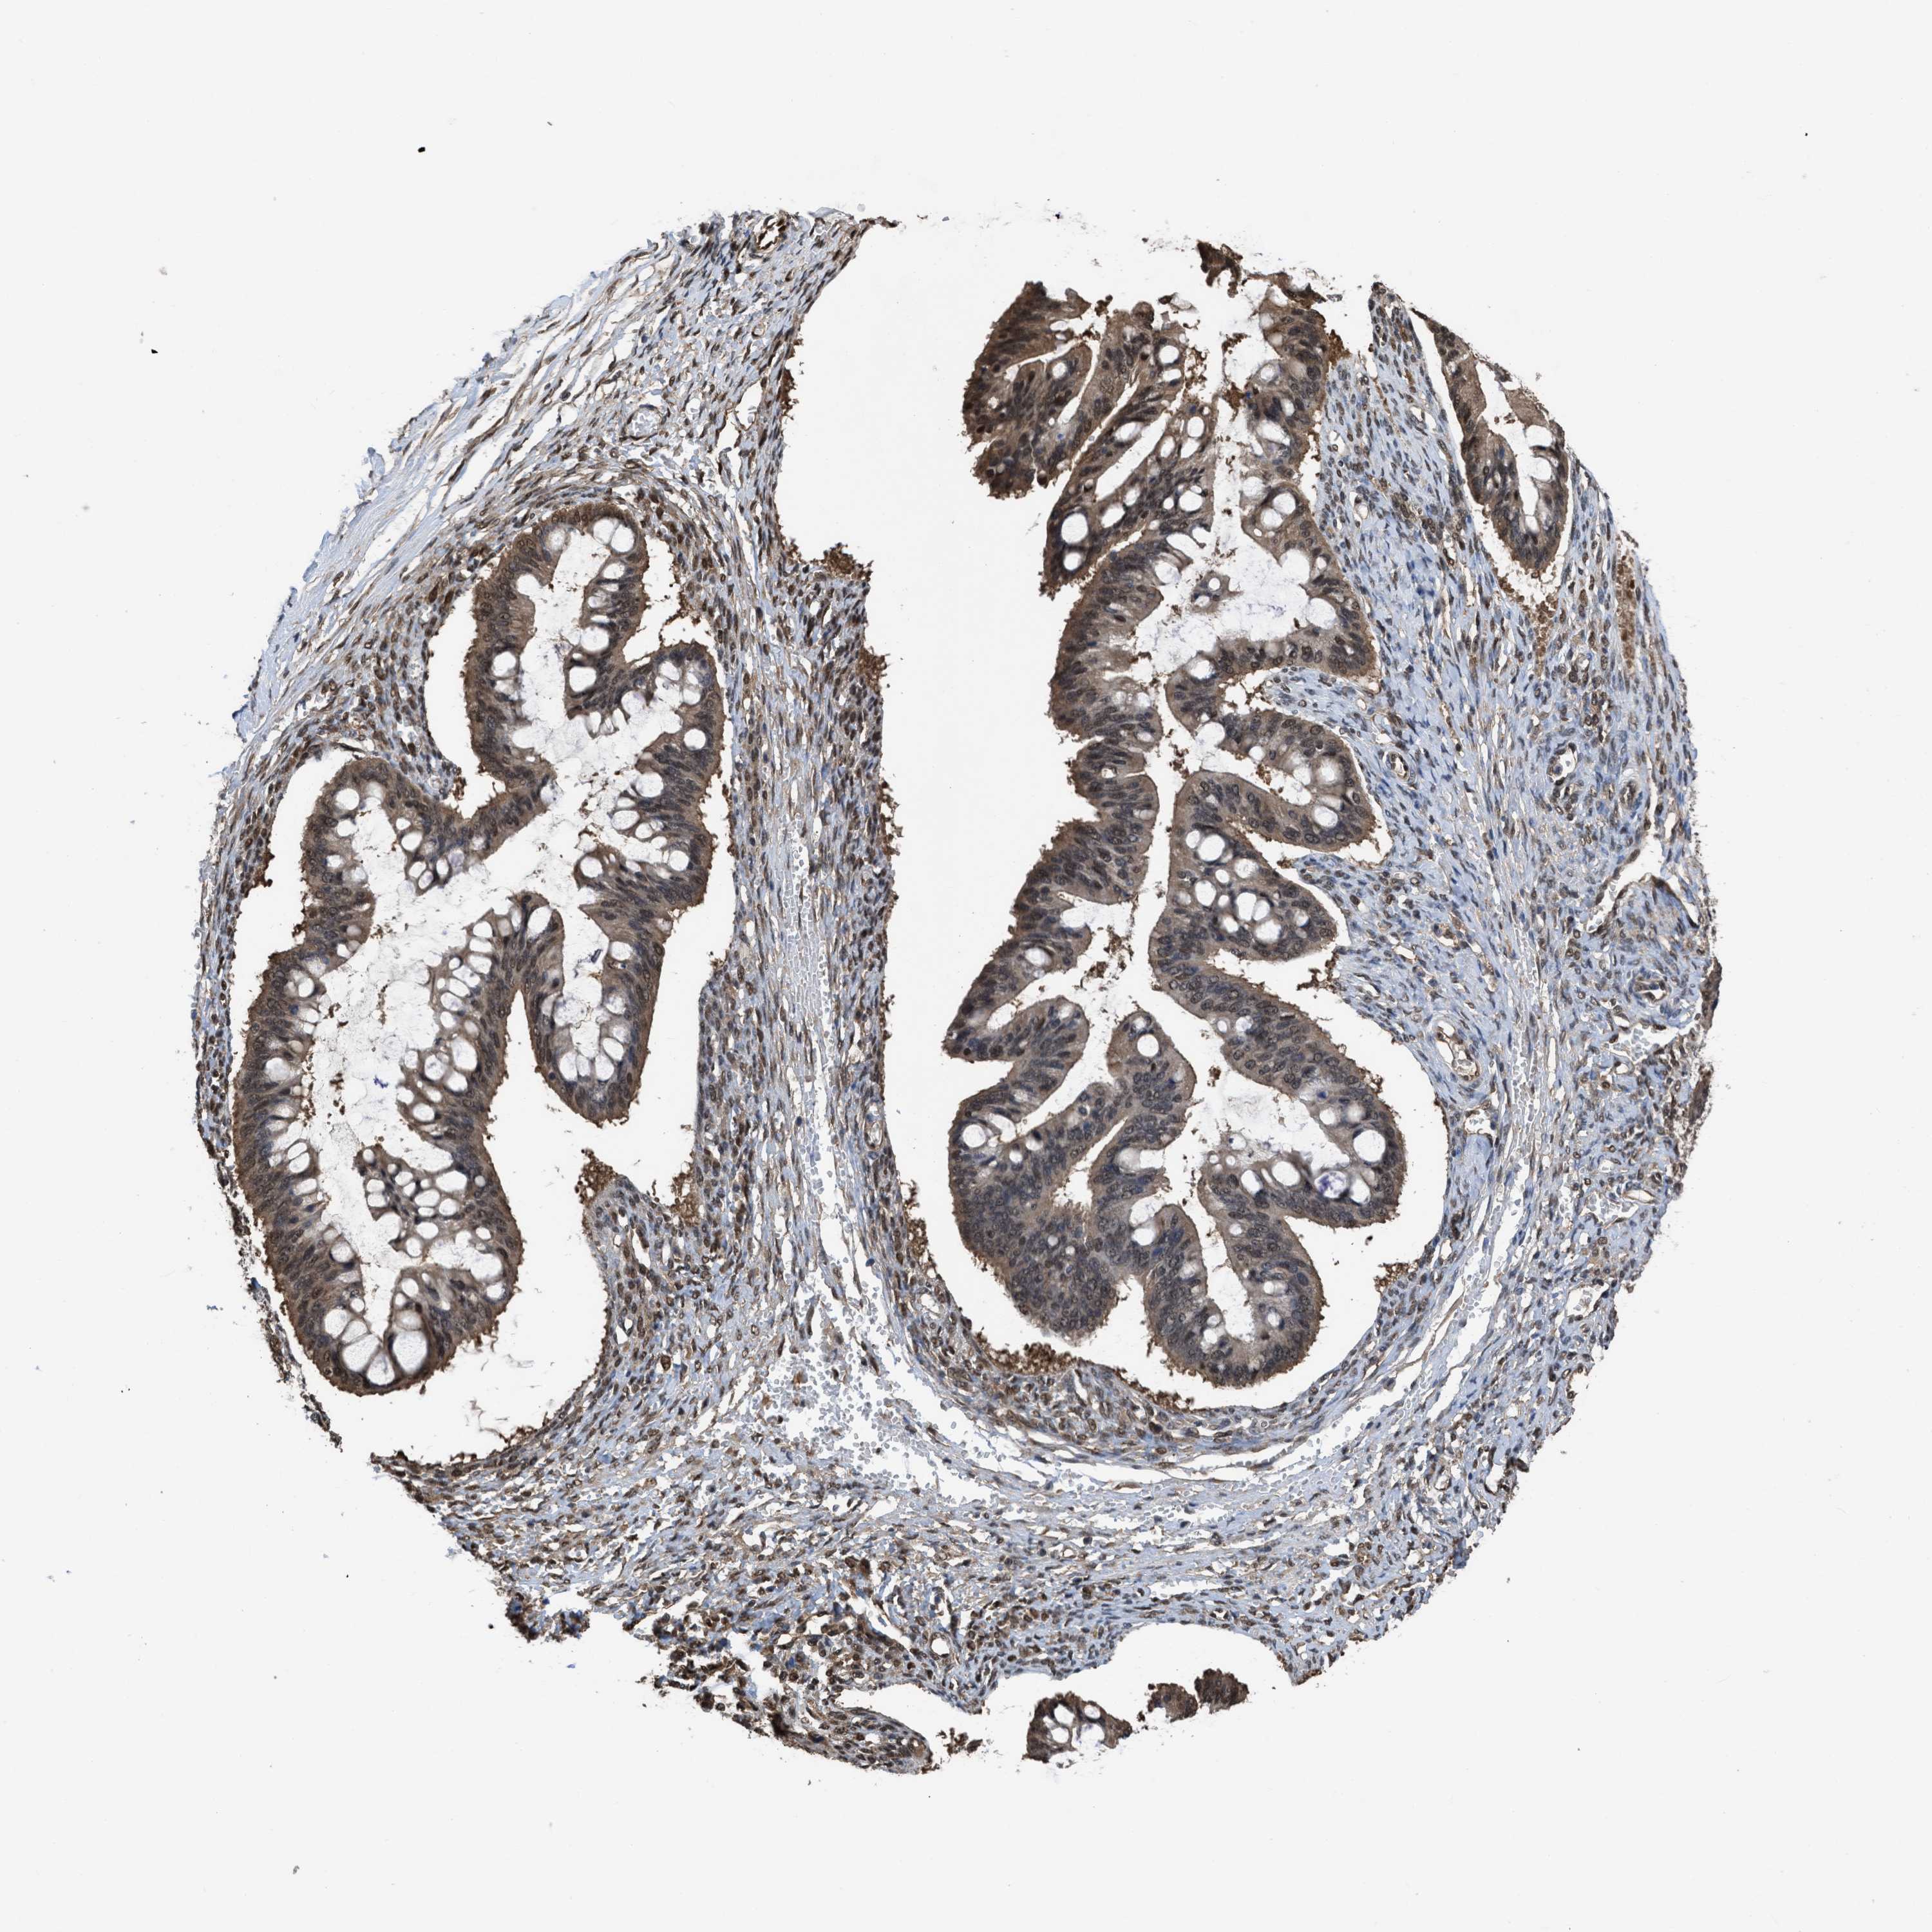

OVARIAN CANCER - Protein expressioni

A mouse-over function shows sample information and annotation data. Click on an image to view it in a full screen mode. Samples can be filtered based on level of antibody staining by selecting one or several of the following categories: high, medium, low and not detected. The assay and annotation is described here.

Note that samples used for immunohistochemistry by the Human Protein Atlas do not correspond to samples in the TCGA dataset.

Antibody stainingi

Antibody staining in the annotated cell types in the current human tissue is reported as not detected, low, medium, or high, based on conventional immunohistochemistry profiling in selected tissues. This score is based on the combination of the staining intensity and fraction of stained cells.

Each image is clickable and will lead to virtual microscopy that enables deeper exploration of all samples and also displays staining intensity scores, fraction scores and subcellular localization as well as patient and tissue information for each sample.

Antibody HPA026918

Antibody CAB013274

Antibody CAB018389

Cystadenocarcinoma, serous, NOS

Carcinoma, endometroid

Cystadenocarcinoma, mucinous, NOS

Carcinoma, NOS